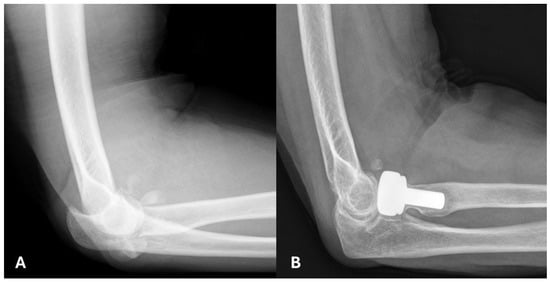

Radiographic analysis of all 14 patients showed varying degrees of implant loosening. In the modular group, eight patients (80%) showed no signs of loosening, one (10%) had mild loosening, and one (10%) had moderate loosening. In the monobloc group, all four patients exhibited loosening, with three (75%) showing mild and one (25%) showing moderate loosening. Mild degenerative changes were observed in two (20%) patients in the modular group and one (25%) patient in the monobloc group. Heterotopic ossification was noted in three patients (30%) in the modular group, none of which were functionally limiting, while no cases were observed in the monobloc group (Figure 2 and Figure 3).

Figure 2. 63-year-old patient with a comminuted fracture of the radial head, who underwent a modular radial-head arthroplasty. (A) Lateral radiograph of the right elbow, before the operation in 2009. (B) Lateral radiograph in 2019, showing heterotopic ossification that does not affect the joint.